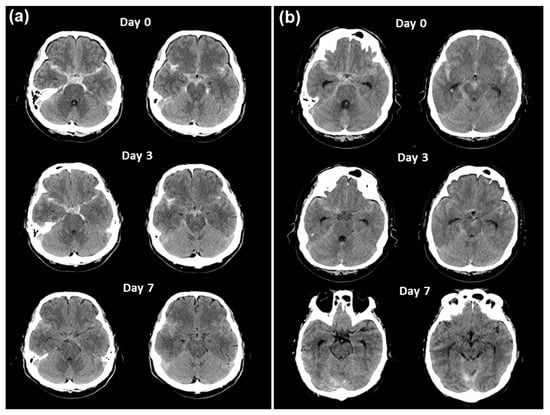

2.2. Contracting Case without Vasospasm

2.3. Clot Density Measurements